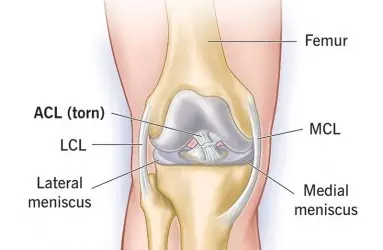

- Artroskopi

- Diz Ekleminde Kireçlenme (Diz Osteoartriti)